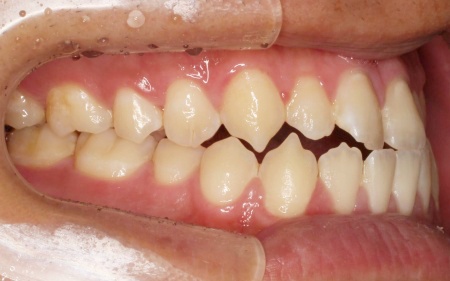

最後に、歯並びと噛み合わせが整い、見た目にも問題がないことを確認し、治療を終了しています。

拝見したところ、上下前歯の先端同士が触れ合う「切端咬合(せったんこうごう)」の状態でした。

通常は上前歯が下前歯をわずかに覆うように重なりますが、患者様の場合は上下前歯の先端がほぼ同じ高さで噛み合っているため、受け口のような印象がみられました。